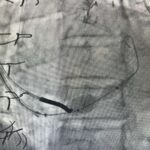

Zabieg wykonywany jest z nakłucia żyły szyjnej i polega na kontrolowanym zwężeniu zatoki wieńcowej przy użyciu rozprężalnego na balonie stentu o kształcie klepsydry. Wskutek zabiegu dochodzi do stopniowego zwężenia pola przepływu przez zatokę wieńcową z redystrybucją przepływu krwi z obszarów o lepszym do obszarów o gorszym ukrwieniu mięśnia sercowego.